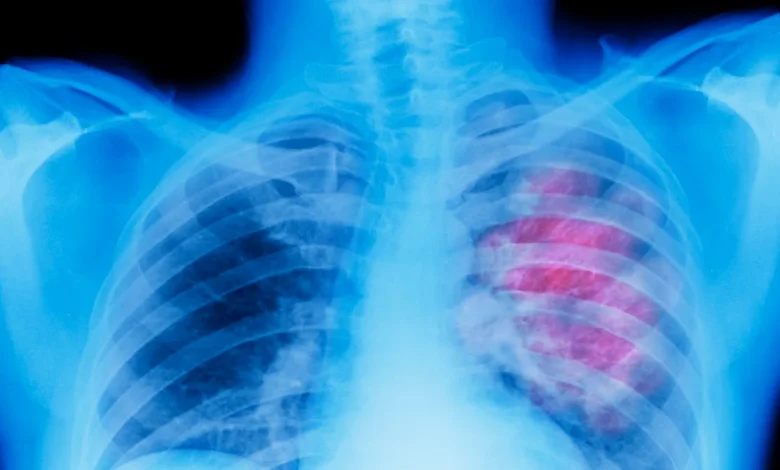

Wie verändern Corona oder die Grippe die Lunge? Forscher haben untersucht, welchen Einfluss schwere Atemwegserkrankungen auf das Krebsrisiko haben. Eine neue Studie ermögliche nun ein „komplettes Bild“.

Menschen mit schweren Verläufen von Covid-19 oder Grippe haben einer Studie zufolge ein erhöhtes Lungenkrebsrisiko. Ein US-Team beschreibt im Fachjournal „Cell“ gleich mehrere Faktoren für diesen Zusammenhang. Es empfiehlt, Menschen nach schweren Corona-Erkrankungen regelmäßig auf Lungenkrebs hin zu testen.

„Ein schwerer Verlauf von Covid-19 oder Grippe kann die Lunge in einen langanhaltenden Entzündungszustand versetzen, der es Krebs später erleichtert, sich dort anzusiedeln“, erläutert Hauptautor Jie Sun von der University of Virginia. Er verweist auf eine einfache Vorsorge durch die üblichen Impfungen: „Die gute Nachricht ist, dass Impfungen diese schädlichen Veränderungen für das Krebswachstum in der Lunge weitgehend verhindern.“